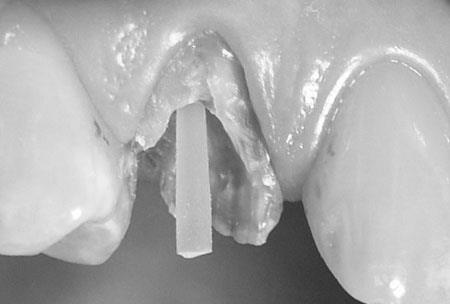

Na zdjęciu poniżej mamy pokazany

wkład z włókna szklanego wystający z kanału. Należy wokół niego odbudować

cementem lub kompozytem brakujące tkanki.

Ogromną zaletą wkładów z

włókna szklanego jest ich biokompatybilność oraz neutralny, białawy kolor.